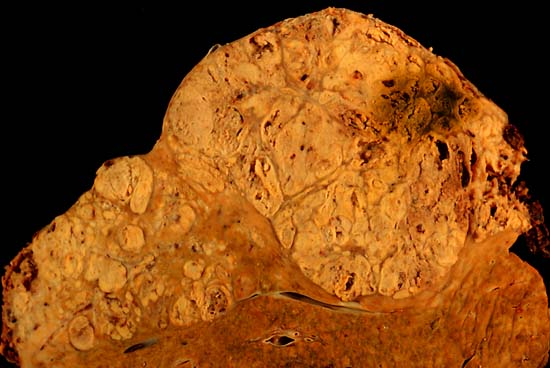

Description Hepatocellular carcinoma

This specimen is from a 50ish woman who presented to the hospital with abdominal pain and ascites. The radiologist recovered what appeared to be whole blood on paracentesis. Cytological exam of the bloody fluid showed no evidence of malignancy. Liver function tests were abnormal, and serologic tests were positive for antibody to hepatitis C. The patient deteriorated rapidly and died within a few days. The autopsy showed this hepatocellular carcinoma occupying much of the volume of a cirrhotic liver. Furthermore, the tumor had invaded the diaphragm and ruptured into the peritoneal cavity, causing the bloody ascites.

The photo shows a view of a longitudinal slice taken through the full length of the liver.